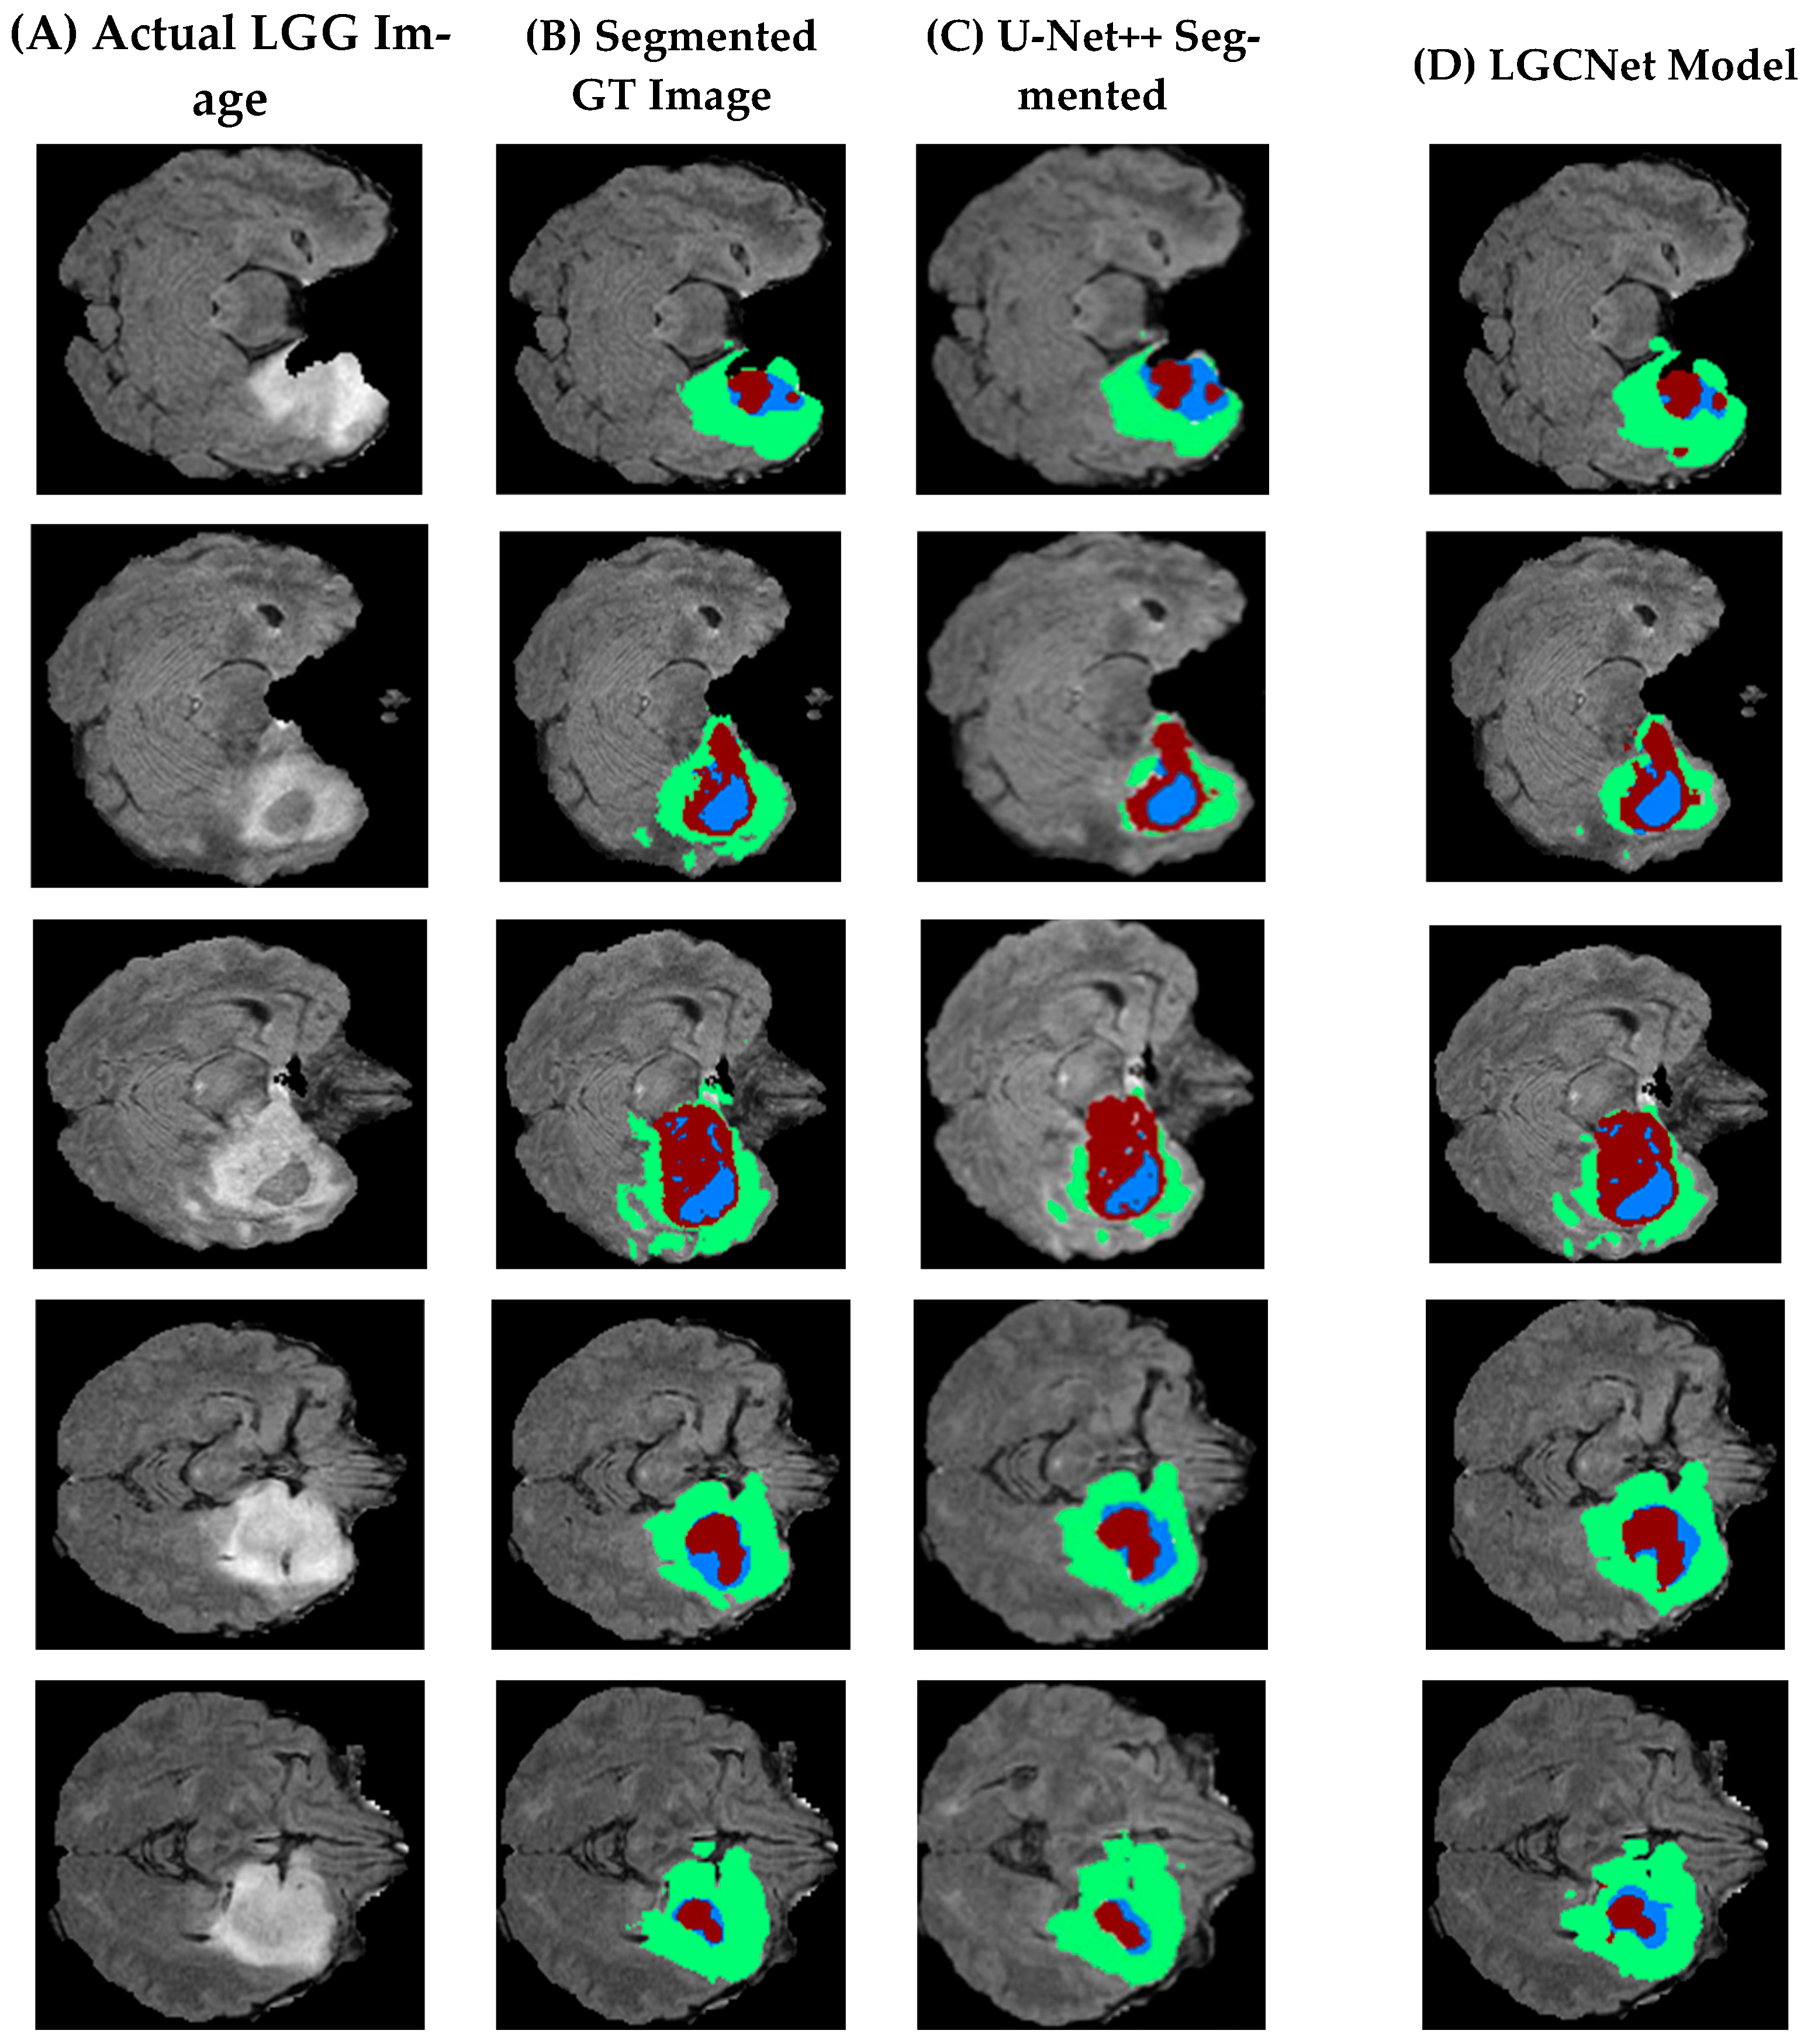

Table 2 presents a visual comparison of the segmentation of the LGG sample, where five different slices are considered. In Table 2, the first row (A) is actual images from the dataset, (B) is segmented ground truth images (C) is existing images segmented using U-Net++, and (D) presents images segmented using the proposed model segmentation. An initial observation shows that the LGCNet model presented in (D) is more accurate than the existing approach (U-Net++). However, it is less accurate due to an imbalance in the datasets.

Figure 9 presents the segmentation of five slices of a brain with an HGG, where Column A shows an actual HGG image, Column B shows a segmented ground truth image, Column C shows an image segmented using U-Net++, and Column D shows an image segmented by the proposed model.

By comparing this figure to Figure 8, it can be noticed that the HGG classification is more accurate than the LGG and that the labels in LGCNet are better than those in the existing model. Moreover, it can be observed that the proposed model is able to identify and segment all three labels (Label 2, Label 3 and label more optimal than the existing model), as shown in Figure 9 and Figure 10.

Figure 9. Segmented images of five slices of a brain with an LGG.

Figure 10. Segmented images of five slices of a brain with an HGG.